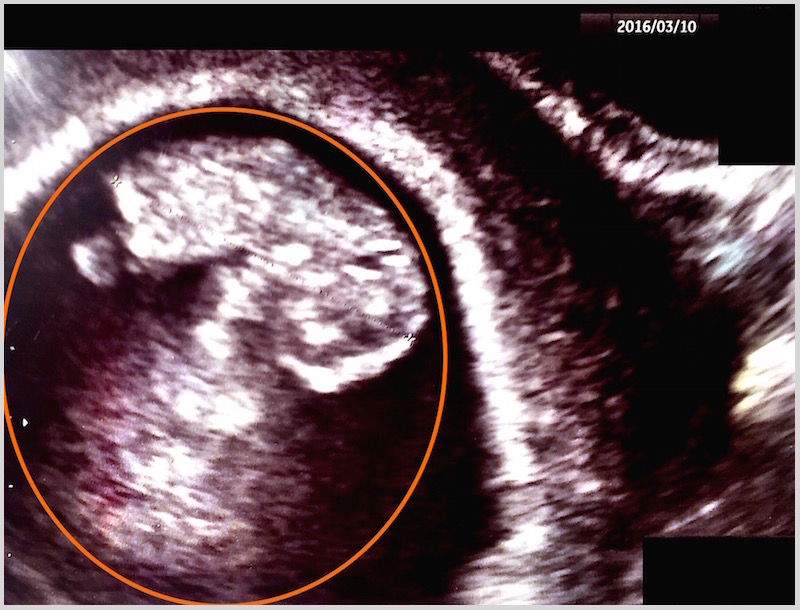

2/29(月) 27診目

26日に検診へ。妊娠7週6日。

エコー検査で問題なし。

後日、エコーの写真を見せて頂き

オレンジで囲っているのが胎児。

(Y.Kさんの掲載許可済み。

日付以外の情報・クリニック名などは消させて頂いております。)